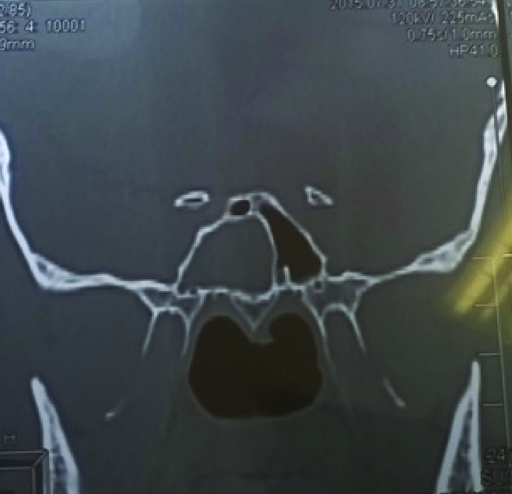

ВВЕДЕНИЕ В настоящее время в связи с распространением лучевых (МРТ, КТ) и визуальных (эндоскопия) методов диагностики наблюдается увеличение количества случаев изолированного сфеноидита [1, 2, 3]. Удельный вес изолированного сфеноидита в общей структуре заболеваний околоносовых пазух (ОНП), по данным литературы, составляет не более 5% [4, 5, 6]. Однако абсолютные цифры с учетом огромного количества случаев воспалительной патологии ОНП могут быть весьма значительными. В структуре синуситов все больше резистентных (устойчивых к лечению) форм, в том числе грибковых [7]. Данные о распространенности патологии весьма скудные, в структуре статистической отчетности стационаров и поликлиник сфеноидит как самостоятельная нозологическая форма отражается крайне редко. В то же время относительно невысокая распространенность нередко обусловливает пассивную позицию специалистов при дифференциальной диагностике поражений клиновидной пазухи (КП). Основное место в дифференциальной диагностике у данной группы пациентов занимают компьютерная томография (КТ) и магнитно-резонансная томография (МРТ). Однако трактовка результатов исследований не всегда однозначна и может приводить как к гипердиагностике, так и, наоборот, к гиподиагностике сфеноидита, выражающейся в недооценке данных лучевой диагностики и обьективной картины и нередко приводящей к развитию хронических и осложненных форм. Пациенты направляются к лор-врачу только после длительного, безуспешного лечения у специалистов смежных специальностей, что влечет высокий уровень гиподиагностики сфеноидита и наличие осложненных форм [8]. Дифференциальная диагностика патологического процесса в пазухе на дооперационном этапе чрезвычайно важна, поскольку необдуманное вмешательство может вызвать тяжелые и даже фатальные осложнения [9, 10]. От 5% до 30% всех изолированных поражений клиновидной пазухи составляют пациенты с неинвазивной грибковой формой [11, 12]. Для хронического сфеноидита характерно латентное (скрытое) течение, которое не всегда диагностируется на ранних стадиях [13, 14]. По данным ряда исследователей, частота патологических находок в клиновидной пазухе при аутопсии лиц, прижизненный диагноз «сфеноидит» у которых не был установлен, составляет от 10% до 68% [15, 16]. Очень важно изучение вопросов ремоделирования в клиновидной пазухе, в том числе явлений остеита при грибковых формах [17]. Осложненное течение изолированного сфеноиди-та - нередкое явление, при этом основным фактором развития осложнений является несвоевременная диагностика. Наиболее часто встречаются осложнения, связанные с вовлечением в патологический процесс глазодвигательных нервов, в особенности VI пары - n. abducens [4, 9, 16]. В литературе можно встретить наблюдения инвазивных, генерализованных форм грибкового сфеноидита с быстрым развитием офтальмологических, интракраниальных и системных (септических) осложнений [7, 12, 14]. Тактика лечения при изолированных поражениях клиновидной пазухи, по данным литературы, различная. Часть авторов считает наличие изолированного сфеноидита, особенно грибковых форм, мукоцеле, абсолютным показанием к операции. Другие авторы при отсутствии осложнений начинают с консервативной терапии [1, 3, 11, 12]. Задачей хирургического лечения у таких пациентов является не только купирование воспалительного процесса, но и создание условий для адекватной вентиляции пазух и предотвращения возможного рецидива. В то же время вопросы дифференцированного подхода к хирургическому лечению недостаточно освещены в научной литературе и носят преимущественно описательный характер. ш ЦЕЛЬ Провести анализ случаев изолированного поражения клиновидной пазух и выявить основные особенности и ошибки при дифференциальной диагностике на догоспитальном этапе. ш МАТЕРИАЛ И МЕТОДЫ В работе приведены данные о лечении 58 пациентов с изолированным поражением клиновидной пазухи, которые находились на стационарном лечении в ГБУЗ НОКБ им. Н.А. Семашко (кафедра болезней уха, горла и носа ФГБОУ ВО «ПИМУ» Минздрава РФ) в период 2015-2018 гг. Возраст пациентов - от 18 до 68 лет. Средний возраст пациентов с изолированным сфеноидитом составил 43 года, среди них превалировали женщины до 35 лет. Гендерное распределение было следующее: мужчины - 21 (30,7 %), женщины - 37 (69,3%). Давность заболевания составила 26±19 дней. Всего в клинике в данный период наблюдались 118 пациентов с различными формами поражения клиновидной пазухи, у 60 пациентов поражение КП наблюдалось как проявление хронического риносинусита (с полипами и без), то есть имело место сочетанное поражение нескольких или всех околоносовых пазух, и данные наблюдения не были включены в исследование. Критерии включения в исследование: рентгенологические (КТ, МРТ) признаки патологического процесса в клиновидной пазухе, специфическая и неспецифическая симптоматика, латентное течение сфеноидита, отсутствие патологического процесса в других околоносовых пазухах. Критерии исключения: сочетанное поражение других групп околоносовых пазух, нозокомиальный сфенои-дит. Такие состояния, как искривление носовой перегородки, вазомоторный/аллергический ринит, гипертрофия носовых раковин, mnchabullosa средних носовых раковин критериями исключения не являлись. Пациенты с впервые установленным диагнозом составили 85% от общего числа, 15% наблюдений - рецидивные формы заболевания, в том числе 5 пациентов были после ранее проведенного оперативного вмешательства (таблица 1). Морфологическая форма Количество наблюдений Полипозный процесс 15 (25,8%) Киста 18 (31%) Мукоцеле 5 (8,6%) Грибковый сфеноидит 12 (20,6%) Инвазивный грибковый сфеноидит 2 (3,4%) Менингоцеле 4 (6,8%) Новообразование 2 (3,4%) Таблица1. Распределение по виду патологического процесса Table 1. Distribution by the type of pathological process При поступлении в стационар проведено обследование пациентов в следующем объеме: клинические анализы, консультации смежных специалистов - невролога, нейрохирурга, офтальмолога (в зависимости от клинических проявлений). Всем пациентам проводилась предоперационная эндориноскопия. При подготовке к оперативному лечению оценивалось наличие у пациента сопутствующих заболеваний, течение которых проявляется симптоматикой со стороны ОНП и может в значительной степени оказывать влияние на течение патологического процесса в полости носа и ОНП: бронхиальная астма, аспириновая триада, персистирующий или интермиттирующий аллергический ринит, а также комбинация данных заболеваний. ш ОБСУЖДЕНИЕ И РЕЗУЛЬТАТЫ В большинстве случаев причиной обращения за помощью был цефалгический синдром. Все пациенты с болевым синдромом первоначально проходили обследование у невролога либо терапевта, им выполнялось МРТ-исследование на догоспитальном этапе. В данной группе пациентов (n=21, 36,2%) 9 человек были направлены к оториноларингологу сразу после получения данных МРТ. 12 пациентов проходили дальнейшее консервативное лечение у невролога либо не получали никакого лечения, несмотря на очевидные данные МРТ-исследования. После МРТ-исследования уточняющее КТ-исследование было назначено только 3 пациентам. Остальные пациенты были направлены в стационар с результатами МРТ. Таким образом, в рамках нашего исследования можно говорить о превалировании МРТ-диагностики в догоспитальном обследовании и игнорировании специалистами КТ-исследования. Симптоматическая картина у исследуемых пациентов весьма вариабельна: от латентных бессимптомных форм до тяжелых цефалгических и офтальмологических проявлений. Мы наблюдали определенную взаимосвязь между симптоматическими проявлениями и морфологической формой заболевания (таблица 2). В целом манифестирующая ринологическая симптоматика наблюдалась не более чем в трети наблюдений. В остальных ситуациях мы наблюдали либо неспецифическую симптоматику (цефалгические и/ или офтальмоплегические проявления), либо бессимптомное течение. Латентные формы поражений КП, когда патологический процесс выявлен случайно при МРТ/КТ-обследовании по другим причинам, составили около 20% от всех наблюдений. Чаще всего это были поражения в виде кисты клиновидной пазухи и мукоцеле (рисунок 1), реже бессимптомное течение наблюдалось при грибковой форме поражения и менингоцеле (рисунки 2, 3). Хирургическое лечение. Всем пациентам проводилось хирургическое лечение, после тщательного анализа КТ-томограмм для уточнения варианта строения клиновидной пазухи и наличия анатомических вариантов строения (клетки Оноди, дигисценции канала внутренней сонной артерии, зрительного нерва и т.д.) (рисунки 4а, 4б). Все оперативные вмешательства выполнялись под общим обезболиванием. Применялись следующие доступы: трансназальный, расширенный трансназальный, трансэтмоидальный, доступ по методике Bolger Box, транскрыловидный (в одном случае) (таблица 3, фото 5, 6). Расширенный доступ (Wormald PJ. 2005, Palmer J.N. 2013) в отличие от традиционного с механическим расширением естественного соустья подразумевает выкраивание короткого (5-10 мм) назосептального лоскута Морфологическая форма Клинические симптомы Головная боль Постназальный затек Голово кружение Назальная обструкция Глазничные симптомы Полипозный процесс/ полипозно-гнойный + +++ - ++ - Киста - - - + - Мукоцеле ++ + - + - Грибковый сфеноидит ++ ++ + + + Инвазивный грибковый сфеноидит +++ ++ + + +++ Менингоцеле + + + - - Новообразование ++ + + - +++ «+» - степень выраженности симптома от + до +++. «-» - отсутствие симптома. Таблица 2. Симптоматические проявления Table 2. The symptomatic manifestation Рисунок 1. Мукоцеле клиновидной пазухи. Figure 1. Mucocele of the sphenoid sinus. Рисунок 2. Грибковый сфеноидит. 2.1 КТ (аксиальный срез); 2.2 Соустье обтурировано полипом. Трансназальный доступ; 2.3 - грибковые массы в пазухе. Figure 2. Fungal sphenoiditis. 2.1 CT (axial cross-section); 2.2 Anastomosis is obturated by a polyp. Transnasal access; 2.3 - fungal masses in the sinus. Рисунок 3. КТ (фронтальный срез). Остеит стенок клиновидной пазухи при грибковом синусите. Figure 3. CT (front section). Osteitis of the walls of the sphenoid sinus in fungal sinusitis. Рисунок 4а. Дигисценция канала внутренней сонной артерии. КТ-исследование. Figure 4a. Dehiscence of the internal carotid artery channel. CT study Рисунок 4б. Дигисценция канала внутренней сонной артерии. Эндоскопическая картина. Figure 4b. Dehiscence of the internal carotid artery channel. Endoscopic image. Таблица 3. Виды хирургических вмешательств Table 3. Types of surgical interventions слизистои ниже и медиальнее соустья пазухи на ножке с питанием от заднеИ септальноИ ветви крылонебной артерии с широким обнажением и резекцией передней стенки пазухи. При этом соустье мы расширяли при помощи бора. Данный способ упрощает задачу в том случае, если естественное соустье не визуализируется и технически не доступно и/или есть необходимость широкого открытия пазухи. Лоскут на питающей ножке используется для закрытия широкого костного дефекта, что способствует его дальнейшей эпите-лизации и минимизирует развитие в последующем остеита. Исследования ряда авторов свидетельствуют о том, что трансэтмоидальный и трансназальный доступ могут с одинаковым успехом применяться при Рисунок 5. 5a - грибковое тело латерального кармана клиновидной пазухи (КТ, аксиальный срез); 5b - расширенный трансназальный доступ (700 эндоскоп); 5c - КТ через 6 мес. после операции. Figure 5. 5a - fungal ball in the lateral “pocket" of the sphenoid sinus (CT, axial section); 5b - extended transnasal access (700 endoscope); 5c - CT in 6 months after operation. Рисунок 6. Менингоцеле клиновидной пазухи. 6а - МРТ (фронтальный срез); 6b - расширенный трансназальный доступ. Пластика ликворного дефекта после удаления менингоцеле (материал - жир). Figure 6. Meningocele of the sphenoid sinus. 6a - MRI (frontal section); 6b - extended transnasal access. Plasty of the liquor defect after the meningocele removal (the material - fat). Рисунок 7. Соустье через 1 год после расширенного доступа. Figure 7. Anastomosis 1 year after expanded access. Рисунок 8. Соустье через 3 года после расширенного трансназального доступа. Рисунок 9. Рецидив полипозно-гнойного сфеноидита через 6 месяцев после операции. причиной рецидива патологического процесса и потребовал проведения ревизионного вмешательства. В одном случае у пациента, которому ранее выполнена сфенотомия по поводу хронического сфеноидита, но не была вскрыта (распознана) клетка Оноди, в которой локализовалось грибковое воспаление, также потребовалась повторная операция. Figure 9. Recurrence of polypous-purulent sphenoiditis in 6 months after surgery. Figure 8. Anastomosis 3 years after expanded access. изолированном поражении пазухи. Трансназальный доступ более безопасен, чем трансэтмоидальный, и является методом выбора при изолированном поражении пазухи при условии, что патологический процесс в пазухе не требует широкой ревизии и/или создания достаточного по объему сообщения в тех ситуациях, когда велик риск рецидива. Осложнений в послеоперационном периоде не наблюдалось. На 5-7 сутки всем пациентам выполнялась эндориноскопия. В срок от 2 до 3 месяцев 11 пациентам выполнено контрольное КТ. Остальные пациенты (из отдаленных районов) не проходили контрольного осмотра. При выполнении расширенного доступа удалось добиться формирования стойкого, эпителизи-рованного соустья во всех случаях (рисунки 7, 8). При полипозно-гнойных формах сфеноидита наиболее часто наблюдались рецидивы заболевания, однако здесь требовалась только противовоспалительная терапия, в том числе орошение пазухи через сформированное соустье (рисунок 9). Частота развития спаечного процесса после вмешательств составила около 20%, при этом только в 3 наблюдениях рубцово-спаечный процесс явился ш ВЫВОДЫ Изолированный сфенои-дит в структуре пациентов, которым проводилось эндохирургическое лечение при патологии ОНП, составил 3% (около 30% от общего числа сфеноидитов). В стационаре пациенты с точно установленным диагнозом «изолированный сфеноидит» на догоспитальном этапе составили не более 12% от общего числа, что связано как с гиподиагностикой, пассивной позицией в отношении патологии клиновидной пазухи у врачей амбулаторного звена, так и с тактическими ошибками. Отмечено превалирование МРТ-диагностики в догоспитальном обследовании и игнорирование специалистами КТ-исследования. Основной метод лечения изолированного сфеноидита - хирургический. Наиболее часто применялся расширенный трансназальный доступ. Необходимо сочетание с медикаментозным лечением в послеоперационном периоде. Требуются дальнейшие исследования с целью изучения особенности/безопасности и клинической эффективности различных эндохирургических доступов. W Конфликт интересов: все авторы заявляют об отсутствии конфликта интересов, требующего раскрытия в данной статье.Об авторах